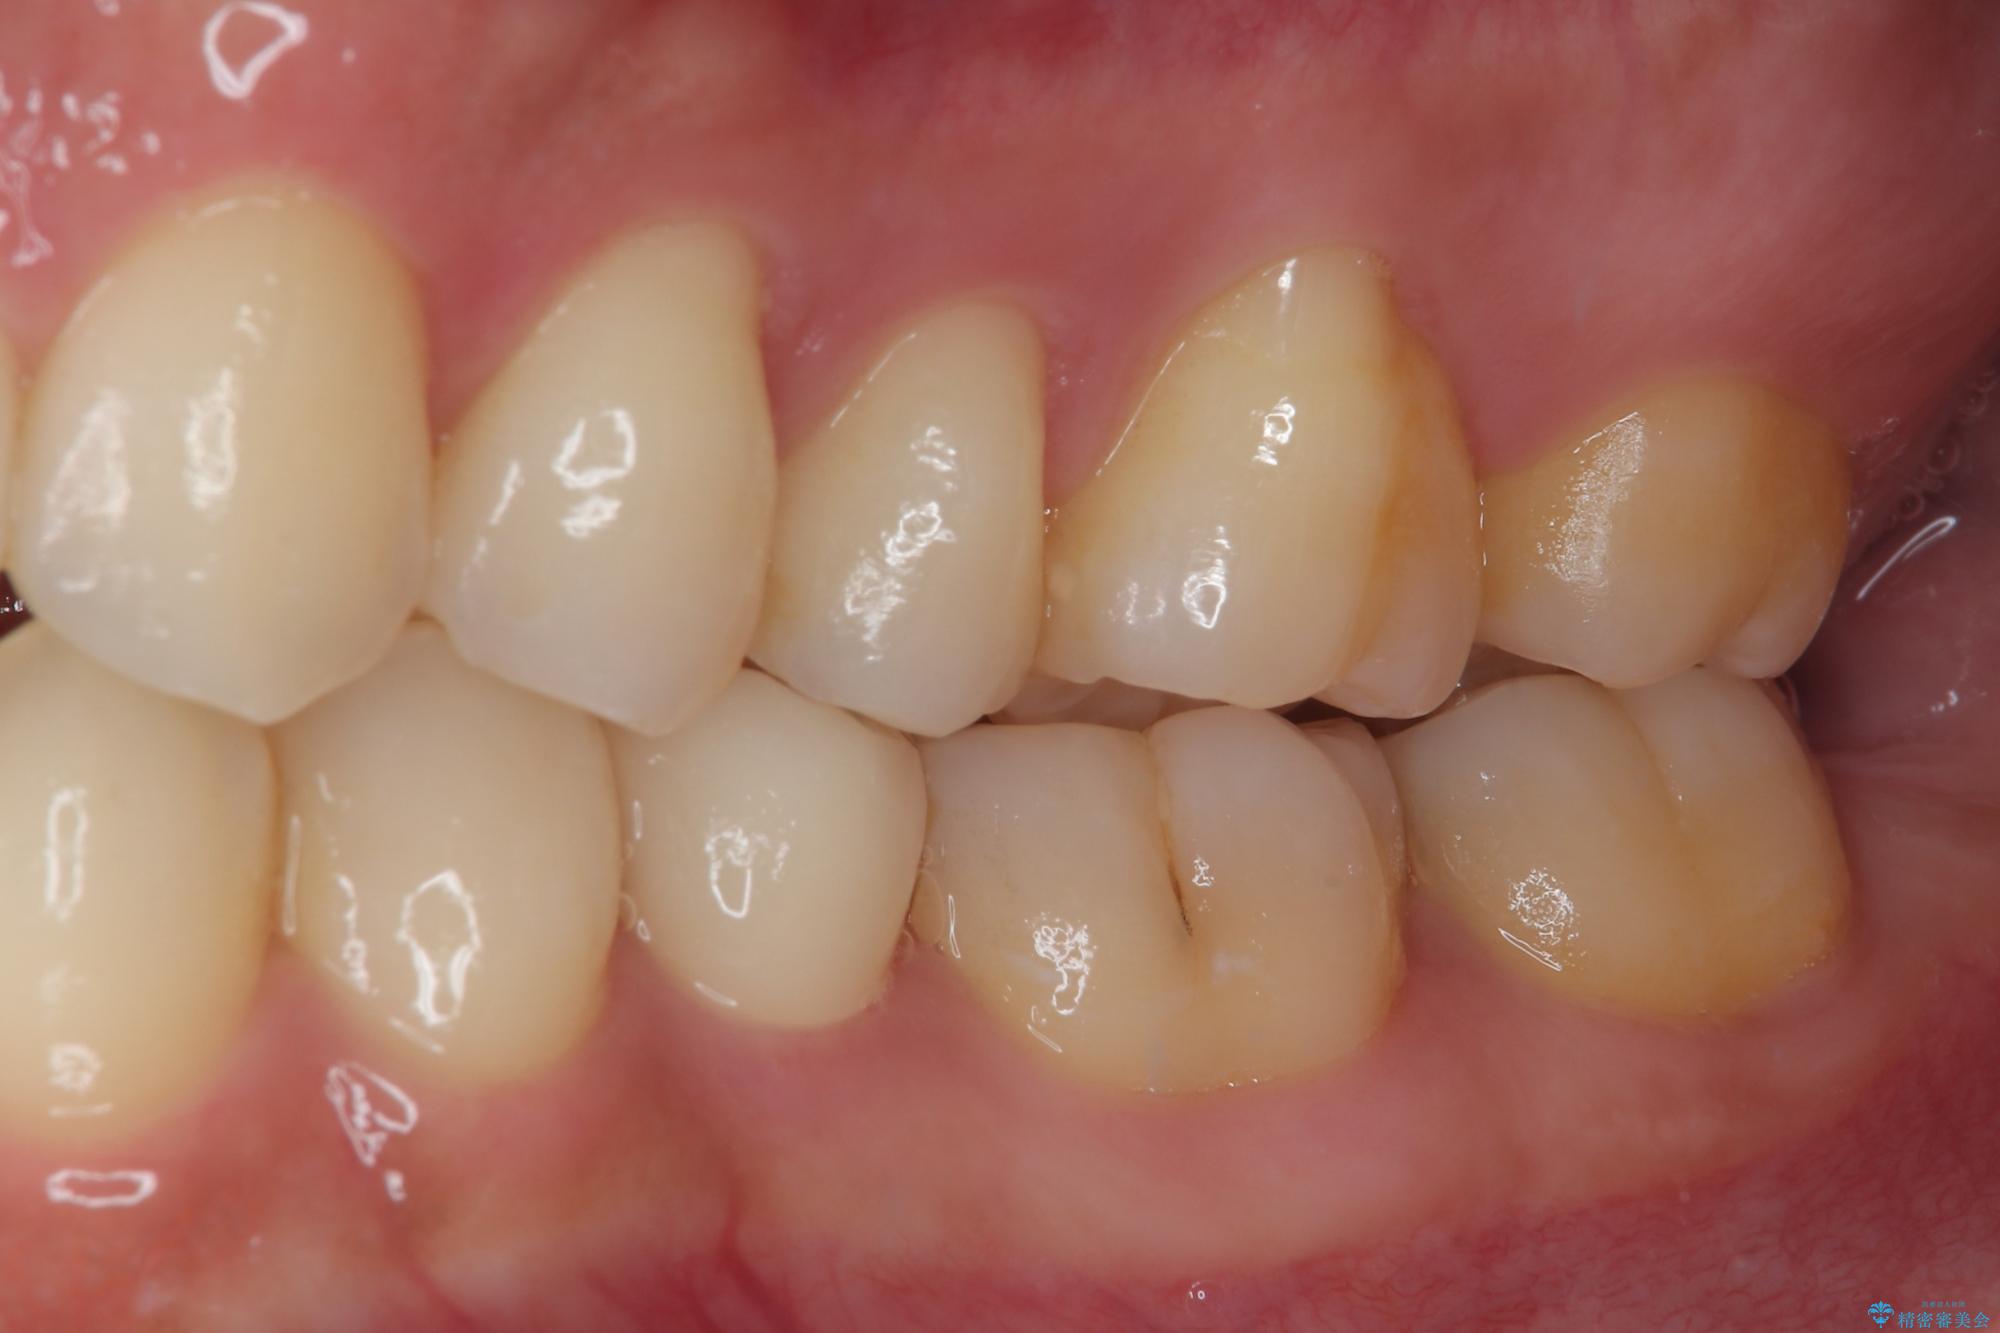

フロスがちぎれることもなくなり、被せものが入っていることを忘れていたと大変喜んでいただきました。適合の良い被せものは二次的な虫歯の再発リスクを低減してくれます。

今後の予定は患者様のタイミングで歯茎から少し見えている親知らず抜歯を行っていく予定です。